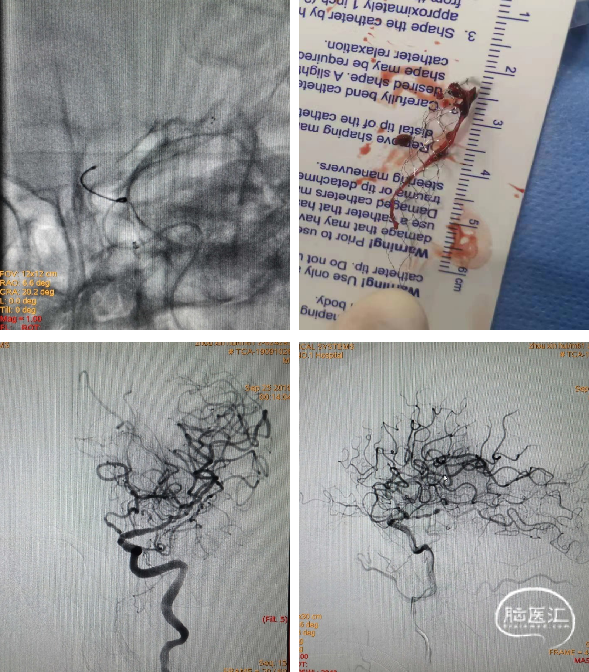

泥鳅导丝导引将8F导引导管置入左侧颈总动脉末端,送入6F中间导管,微导丝导引微导管送至颈内动脉远段,冒烟显示眼动脉以下颈内动脉显影,但血管内充盈缺损明显,以上血管未显影。6F中间导管无法通过颈内动脉起始部,提示串联病变:颈内动脉起始部重度狭窄,狭窄以上管腔内大量血栓形成。采用4*30mm球囊扩张颈内动脉起始部,跟进中间导管,抽出大量血栓,但远段血管仍不显影,考虑大脑中动脉闭塞。

微导丝探查至大脑中动脉M2段,跟进微导管,“冒烟”显示远端通畅。边缓慢回撤微导管,边“冒烟”显示M1段造影剂充盈缺损,呈“轨道征”表现,表明血栓位于该处。

将Reco 4*20mm取栓支架送入血栓处,支架释放5min后,中间导管连接50ml注射器负压抽吸,撤出支架,成功拉出血栓。再次造影显示大脑中动脉M1段开通,但血管壁毛糙明显,经中间导管推注替罗非班7ml避免内膜损伤急性血栓形成。